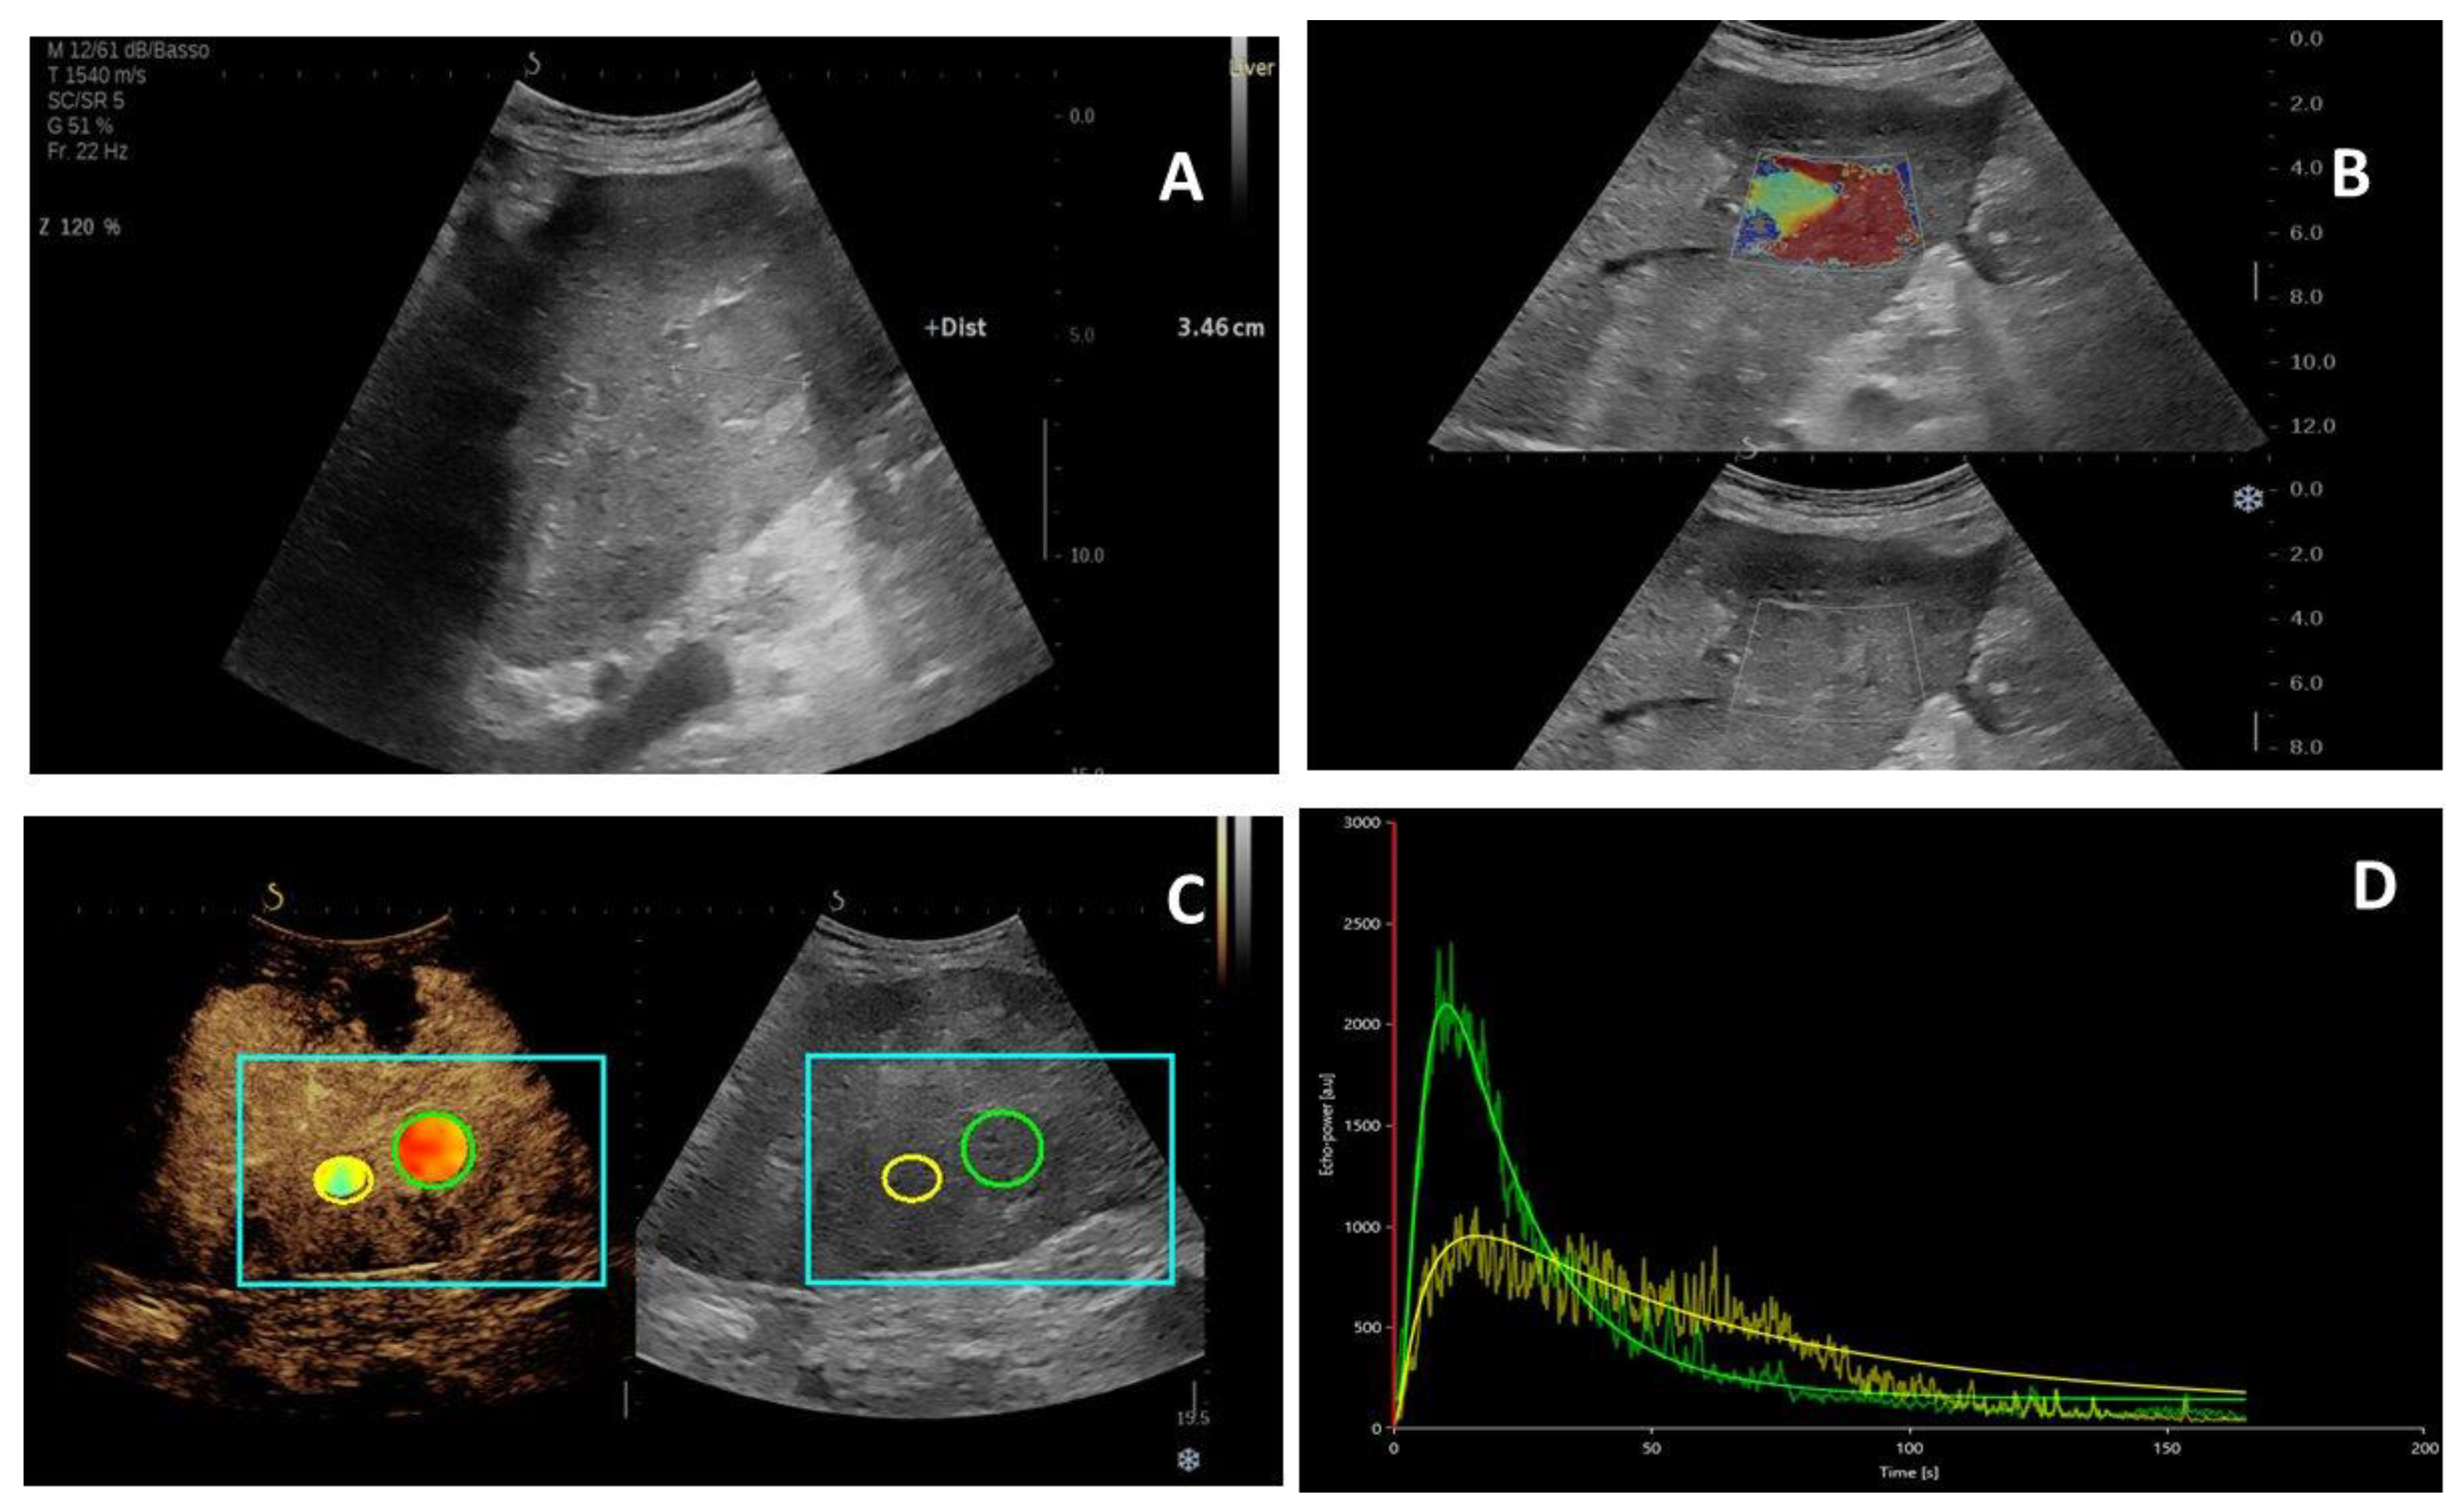

2.2. US Imaging Characteristics